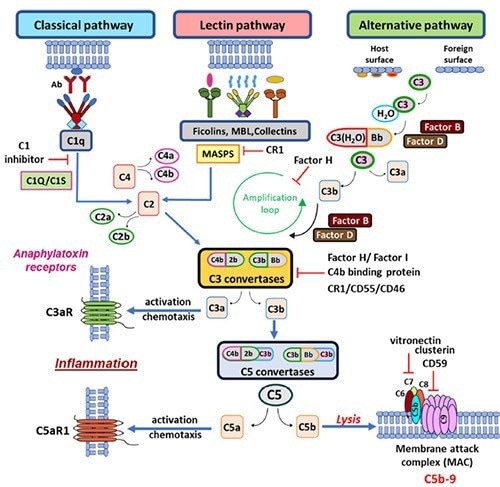

The complement system has more than 50 soluble and membrane-bound proteins. In innate and adaptive immunity, complement is essential for eliminating foreign pathogens and apoptotic cells. It is also linked to human pathological conditions, tumor growth, and tissue regeneration.

The complement cascade pathways. Image Source: https://doi.org/10.1186/s12931-023-02657-2.